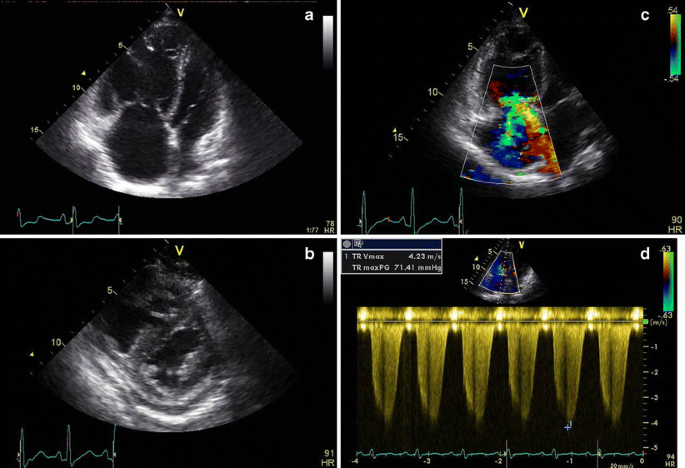

Echocardiography is the principal screening tool for PH. However, it has important limitations in accuracy of estimating pulmonary pressure. Although there are data showing a good correlation between echocardiographic findings and invasive measurements, there are also several studies reporting significant differences [1719]. Another limitation is the fact that a measurement of the tricuspid regurgitation (TR)velocity to estimate PAP is not possible in a significant proportion of patients due to lack of TR or a poor acoustic window. In addition to PAP estimation indirect signs of elevated PAP such as pulmonary regurgitation velocity, acceleration time of the antegrade Doppler signal across the pulmonary valve and signs of right ventricular (RV) pressure overload or failure should always be documented to increase accuracy of the method (Fig. 3a-d). In patients with symptoms and increased risk for developing PAH, additional invasive evaluation is necessary, also in case of normal echocardiographic findings. Nevertheless echocardiography remains the non-invasive key investigation and also plays an important role in classification of PH by excluding or identifying systolic or diastolic left heart dysfunction and valve disease or congenital heart disease as associated condition and gives important prognostic information [20, 21]. The presence of pericardial effusion and a tricuspid annual excursion (TAPSE) <15 are predictors of worse outcome in PAH.

Fig. 3

figure 3

a-d echocardiography in a patient with portopulmonary PAH. a and b apical four-chamber view and parasternal short-axis view showing an enlarged and hypertrophic right ventricle and a flattened interventricular septum, compromising the left ventricle. Pericardial effusion is present, a predictor of worse outcome. c and d Significant tricuspid regurgitation with a flow velocity of 4.23 m/sec in accordance with a pulmonary artery pressure of 71.4 mmHg + right atrial pressure)